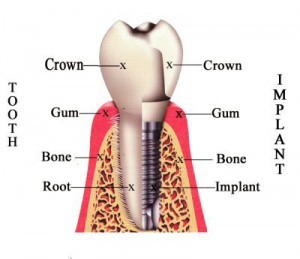

Dental implant is replacement tooth root which provide a strong foundation for fixing new teeth. They are one of the most latest advances in dentistry for making new teeth.

Dental implant surgery is a specialised & skill full procedure of dentistry, Because, It includes application & knowledge of periodontology, prosthodontics & oral surgery.